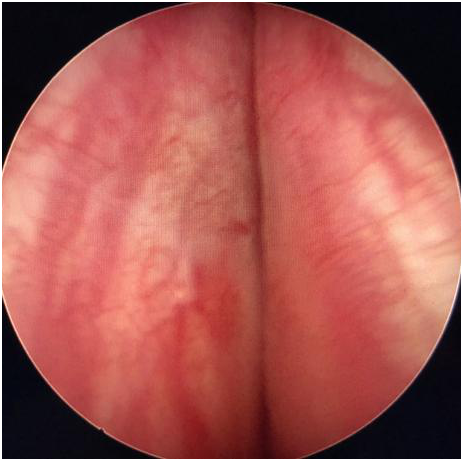

視察前列腺